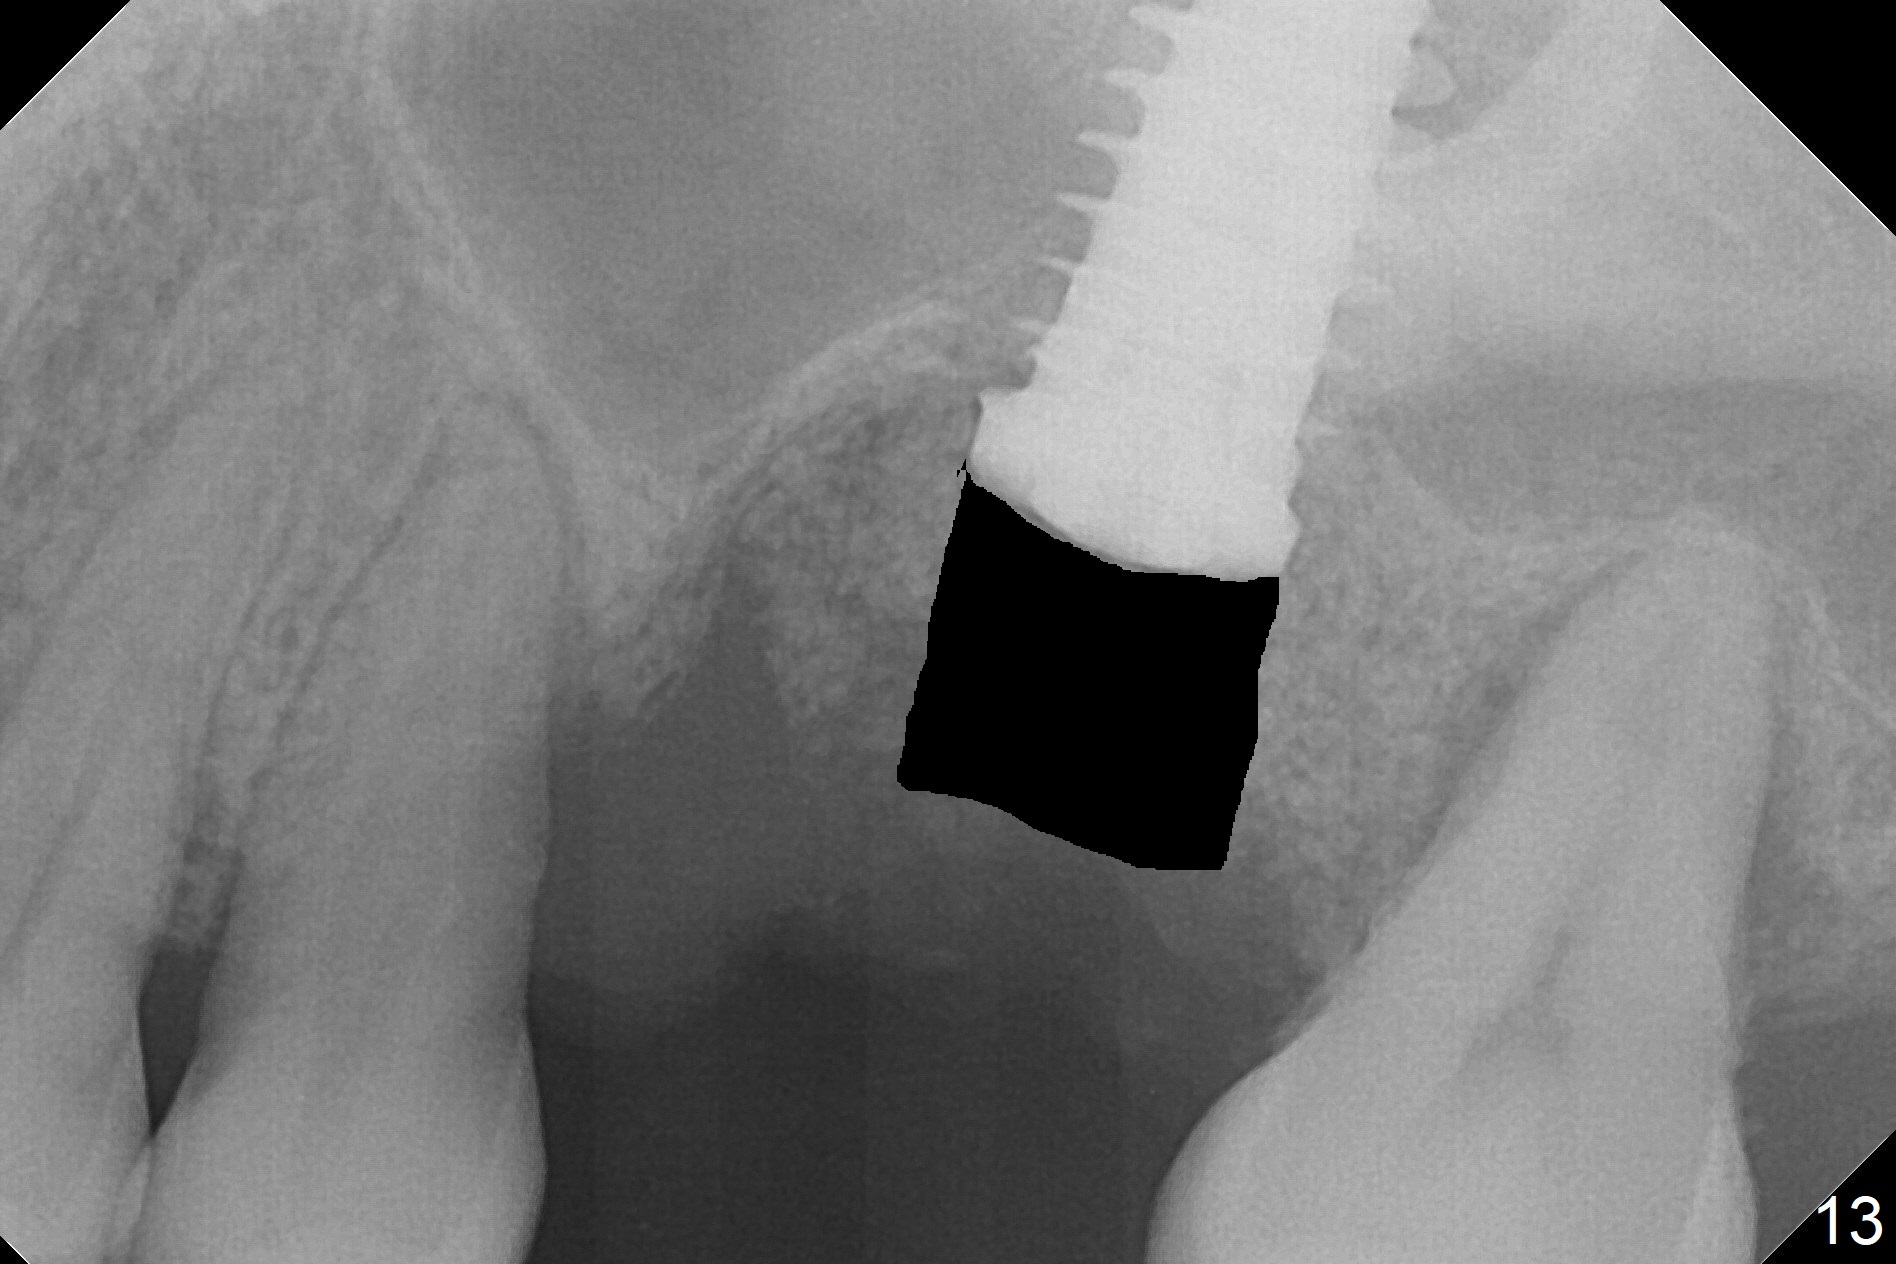

Questions for Dr. Wang: Can we remove the coronal portion of the bone (Fig.13) and back up the implant (Fig.14 arrow) 4-5 months postop for easy restoration?  If it is not a good option, can we produce pair abutments with 5 and 7 mm cuffs?

1.  It seems that the implant was placed deeper than intended, (he had no choice but to do so because of the enlarged osteotomy)

2.  I predict that the bone above the implant will only be about 1-2 mm. In other words, your idea of backing up the implant will only be about 1-2mm possible.

3.  Assuming that 1-2mm of backing up the implant will be sustainable, since stability will still be secure, let heal a month more after backing up, then use cuff 4 abutment to restore.

In fact, there is no coronal bone for the implant to be backed up.  Therefore, impression is taken after uncover and insertion of a 5.5x5.7(4) mm abutment.

There is a mushroom around the implant nearly 5 months postop/immediately before cementation (Fig.21).  The bone density around the implant is low (Fig.22-24' *).